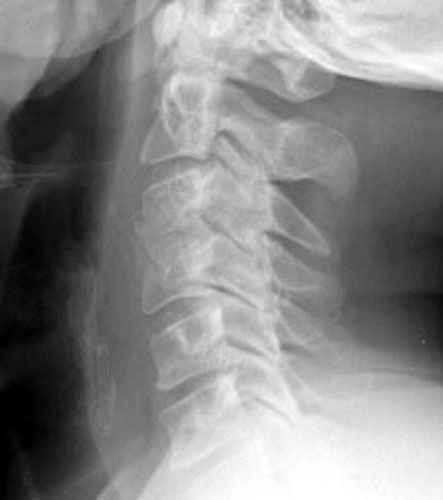

48 y.o. male with a history of alcohol abuse, depression and degenerative joint disease who is complaining of severe pain in his right neck and shoulder radiating down to his right third and fourth digit. The patient underwent anterior cervical disc fusion. Four months after the initial surgery, the patient still had pain but this time numbness was on flexion mainly and localized to the C5 region.

Lateral flexion and extension radiographs taken 6 months after surgery demonstrate incomplete graft incorporation (delayed healing). Furthermore, with flexion there is anterolisthesis of C4 on C5 (one level below the fusion) by 2-3 mm.